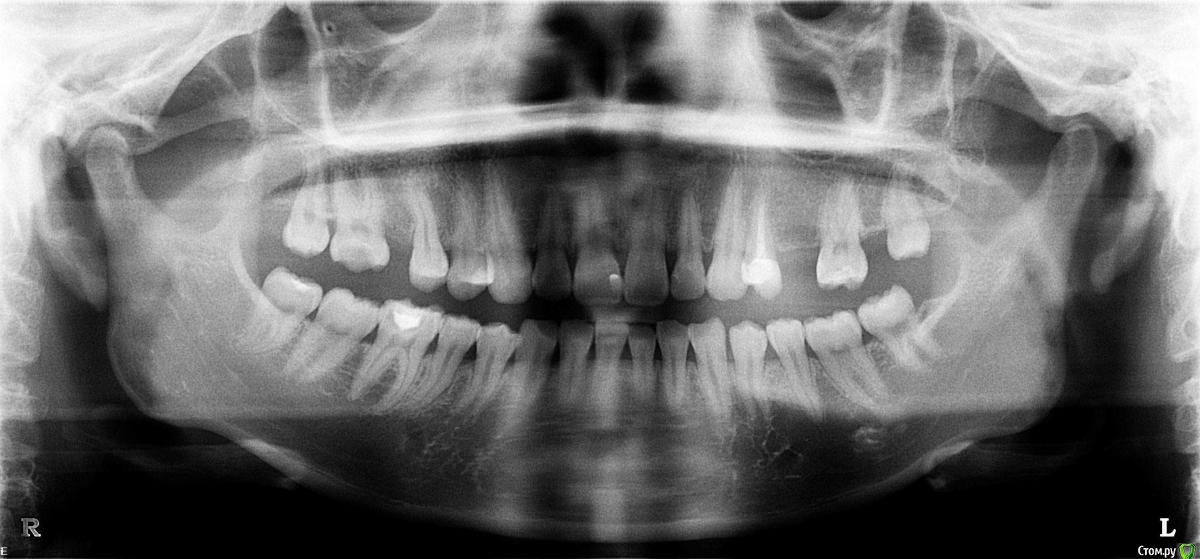

Яна Баировна Опубликовано 15 декабря, 2016 Поделиться Опубликовано 15 декабря, 2016 (изменено) Уважаемые врачи прошу подсказать по моей проблеме. У меня полтора месяца назад начали кровоточить десны между зубами 4-5-6 с правой, нижней стороны. Сходила в гос поликлинику к стоматологу - терапевту, которая сказала что у меня гингивит и сделала чистку ультразвуковую, после которой у меня ещё начали кровоточить передние нижние зубы. Врач посоветовала полоскания содой, солью и йодом чтобы уменьшить отёк, но если не улучшится то обратиться к парадонтологу. Спустя 10 дней отёк уменьшился но кровоточивость оставалась. Затем я сходила к другому врачу - пародонтологу, который сказал, что нужна глубокая чистка, (по цене не дёшево). Я уведомила его о том что неделю назад уже делала чистку, но парадонтолог сказал что нужна именно глубокая чистка, а также он направил сделать панорамное ОПТГ. Так же при визуальном осмотре он сказал что наблюдается начальная стадия парадонтита на однёрке снизу справа. Далее я пошла к первому врачу из поликлиники, которая чистила мне до этого, на дочистку. Но забыла выяснить, сделала ли она глубокую чистку на этот раз или это снова что-то не то?. Параллельно я консультировалась с третьим врачом, которая при внешнем осмотре сказала, что на переднем нижнем зубе образован "патологический" карман и его нужно срочно лечить - признаки пародонтита. Я сходила и сделала снимок панорамный, который тут представлен, но консультации по нему ещё не получила. По снимку не совсем понятно, это брак снимка (засвеченный и размытый именно тот зуб про который говорили врачи)? Подскажите, на снимке в каких местах виден пародонтит и вообще есть ли он? Уважаемые врачи, мне на визитах все говорили разное и тянули на лечение именно у них, но хотелось бы независимого мнения от специалиста! Не хочу и не могу каждый разплатить за возможно ненужные процедуры. Пожалуйста подскажите что-то по снимку. Изменено 15 декабря, 2016 пользователем Яна Баировна Ссылка на комментарий

Ker Опубликовано 16 декабря, 2016 Поделиться Опубликовано 16 декабря, 2016 Насчет парадонтита не поскаду, но зуб 4.6 надо лечить, под пломбой кариес и большой. Ссылка на комментарий

red_butler Опубликовано 16 декабря, 2016 Поделиться Опубликовано 16 декабря, 2016 Для полноценных ответов нужен очный осмотр, но по снимку похоже что пародонтит уже есть. Требуется консультация ортодонта и ортопеда. Ссылка на комментарий